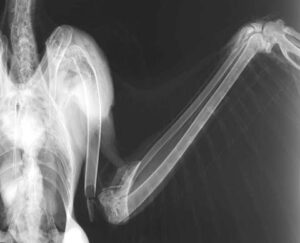

足環から去年生まれの若鳥であることが判明しました。新天地を求め、親元を離れた矢先の交通事故だったのでしょう。精密検査の結果、上腕骨が肘に近いところで折れ、人でいう手首に近いところの骨も粉砕骨折していることが分かりました。